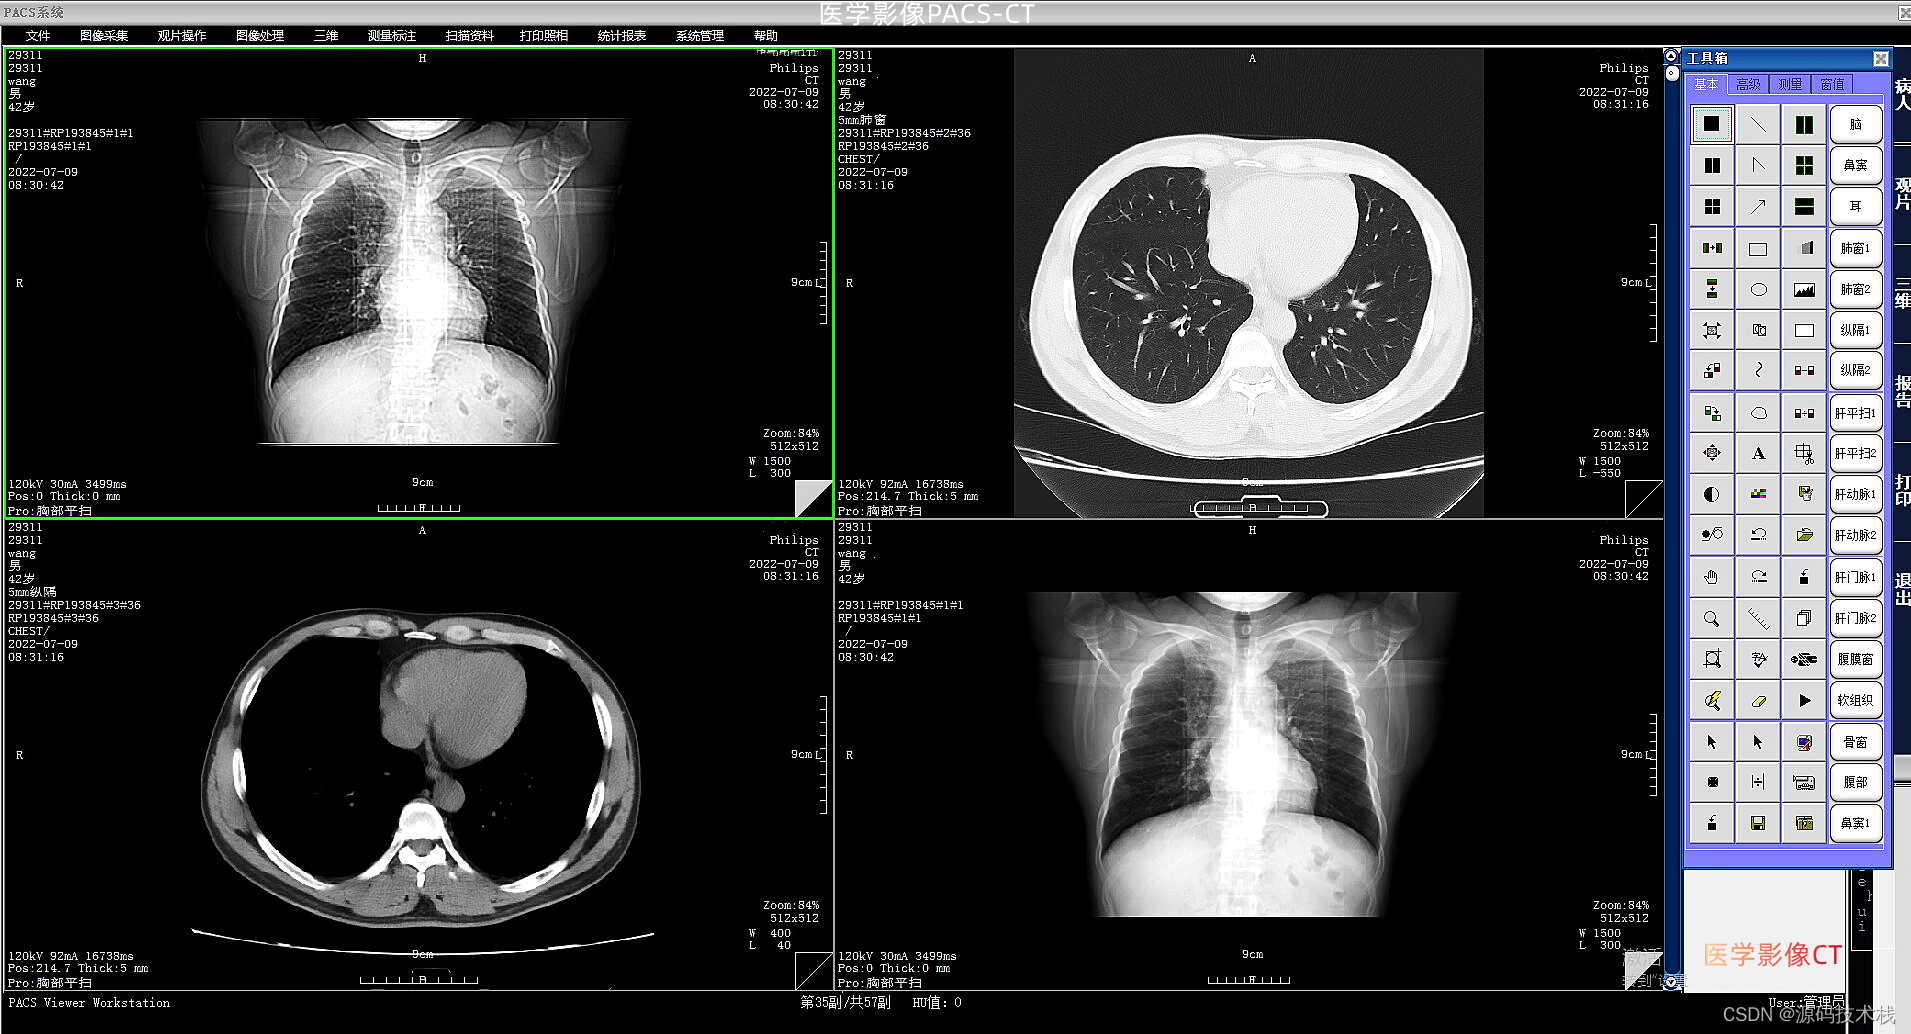

下面就是我们平时大家所做的CT平扫图像:

是基于平扫和各种冠状位、矢状位及水平位的数据,用后期电脑重新合成的数据。将获取的冠状位、矢状位和水平位的数据整合后还原出器官三维立体的形象,可以直观地看到何处有病变,而且根据血流的多少添加色彩,看起来就更加直观。